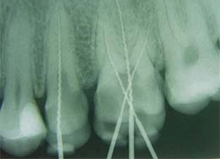

| Der Zahnarzt wird den entsprechenden Zahn betäuben und aufbohren. Dann wird mit nadelähnlichen Instrumenten in den Nervkanal eingegangen und der Nerv herausgezogen. Daraufhin sollte ein Röntgenbild gemacht werden, um zu klären, wie weit die Nadeln in den Zahn eindringen müssen.